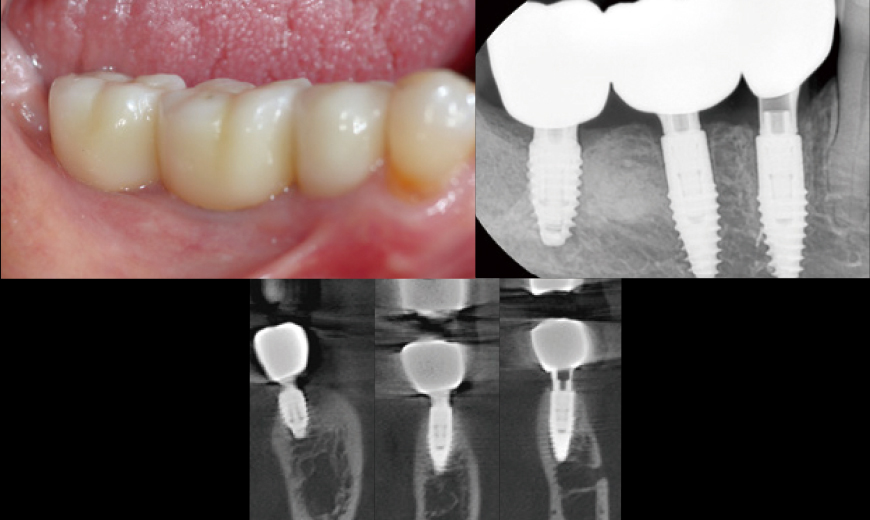

Fig 11

Intraoral Clinical Images, Radiographs, and CBCT Scans at Three Months After Loading Although this represents a relatively short follow-up period, the clinical and radiographic evaluation at three months post-loading showed comparable outcomes to conventional Blue Diamond (BD) implant cases, demonstrating no signs of compromise in stability or bone response.